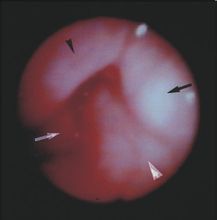

纖維支氣管鏡檢查用於支氣管腫瘤、狹窄、異物的診斷和治療,肺穿刺活檢對肺纖維化、腫瘤等意義重大。

2.喉及氣管內異物

多見於5歲以下幼兒及昏迷患者。異物引起高度吸氣性呼吸困難,嚴重者可窒息。異物引起高度吸氣性呼吸困難,嚴重者窒息。異物進入氣管內引起刺激性咳嗽,進而發生阻塞性肺氣腫,肺不張與肺感染等。

多見幼兒,起病急驟,高熱,哮吼樣咳嗽,聲音嘶啞,呼吸困難常呈晝輕夜重,喉鏡檢查無灰白假膜。